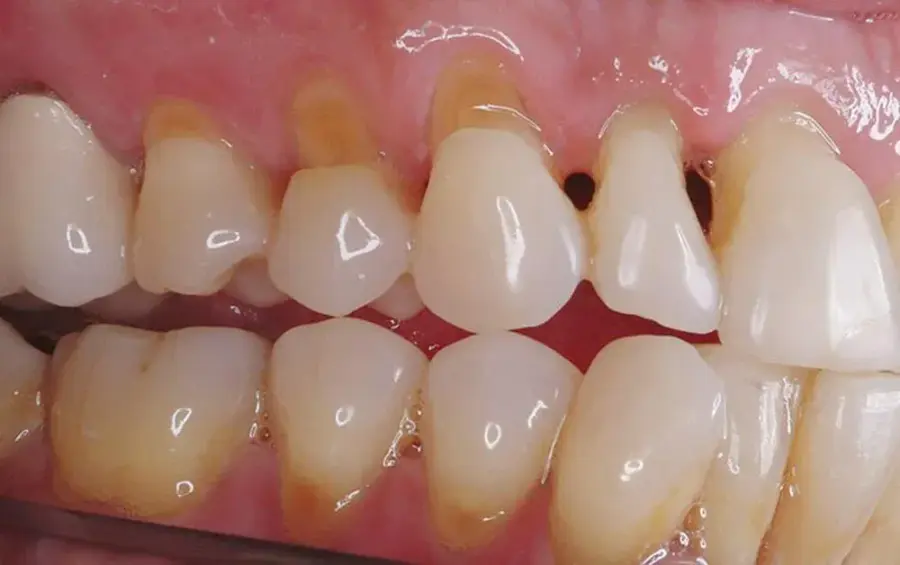

Mòn cổ chân răng là một bệnh lý thường xuyên xảy ra nhất là đối với những người lớn tuổi. Đây là hiện tượng lớp cổ răng mất đi lớp men răng, dẫn đến tình trạng xuất hiện các rãnh sâu, lõm vào tạo hình chữ V ở mặt ngoài răng, sát viền lợi. Mòn cổ chân răng thường xảy ra ở các răng hàm nhỏ, răng 4, 5, 6 và các răng cửa.

Tình trạng mòn cổ răng sẽ gây mất thẩm mỹ và khó chịu cho mọi người. Bạn sẽ gặp trở ngại trong giao tiếp, đau nhức, ê buốt răng nghiêm trọng. Một số trường hợp nặng chưa được chữa trị kịp thời còn gây nên tình trạng lung lay, gãy răng.

Việc cao răng tích tụ lâu ngày, không được vệ sinh làm sạch sẽ gây nên tình trạng đẩy nướu răng xuống dưới (tụt nướu răng). Khi nướu bị tụt, các chân răng cùng lộ ra và dễ bị bào mòn bởi nước bọt hoặc các chất trong thức ăn hằng ngày bám vào. Vậy nên chúng ta dễ gặp tình trạng đau nhức và ê buốt răng do mòn cổ răng.

Một số bệnh lý khác như viêm quanh răng cũng gây nên hiện tượng tụt lợi và làm lộ ra lớp chân răng. Dưới những tác động ăn nhai hằng ngày, lớp chân răng sẽ bị bào mòn dần do độ cứng thấp.